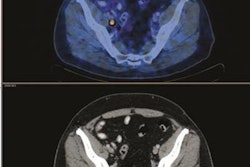

FDG-PET/CT before treatment (A) shows an anal tumor on axial slices and a left inguinal node (black arrow). FDG-PET/CT four months after chemoradiotherapy (B) shows persistent increased FDG uptake in anal canal (noncomplete metabolic response) but complete regression of inguinal node uptake. Persistent disease was proved by biopsy. Images courtesy of JNM.Patients are most often treated with radiotherapy and chemotherapy, with a five-year disease-free survival rate of 67%, they wrote. For patients with disease recurrence or progression, surgery is the most common course of action.